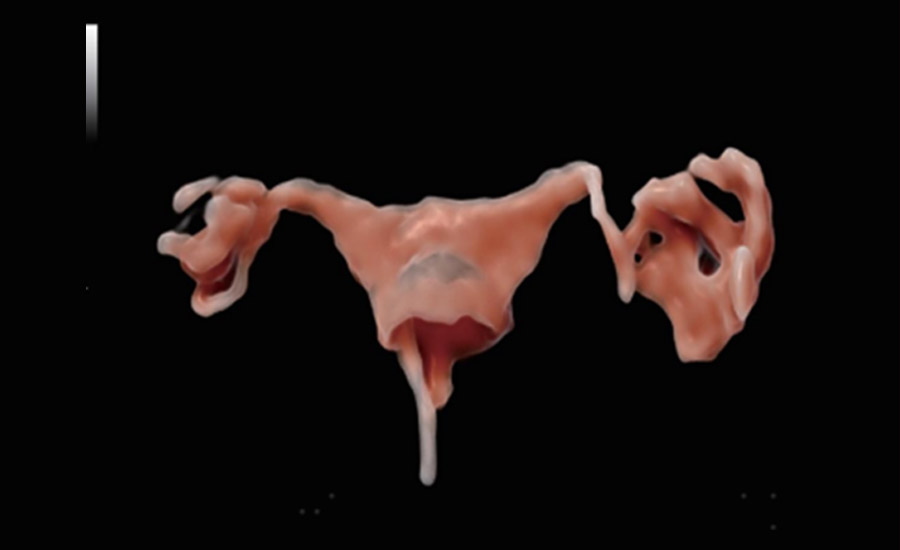

UMA (Ultra-Micro Angiography)

The innovative technology breaks the bottlenecks of traditional Doppler imaging. With ultra-high spatial resolution and flow sensitivity, it allows detecting super-subtle and super-slow flow perfusions, thereby extending the clinical application of qualitative and quantitative ultrasound evaluation in fetal brain, kidney, placenta, endometrium, ovary, etc.

Combining advanced algorithms and domain-specific knowledge, the innovative Smart Scene solution enables auto identification of tissue characteristics and provides organ-specific diagnosis with full-stack intelligence. Based on auto scenario identification, the solution not only realizes smart 2D scanning with auto settings and measurements, but also delivers 3D full-stack intelligence in every step from volume imaging optimization to the difficult 2D plane acquisition, and quantification throughout whole procedure. It helps a lot in reducing the dependency on clinical skills, while increasing diagnostic accuracy, confidence and efficiency.